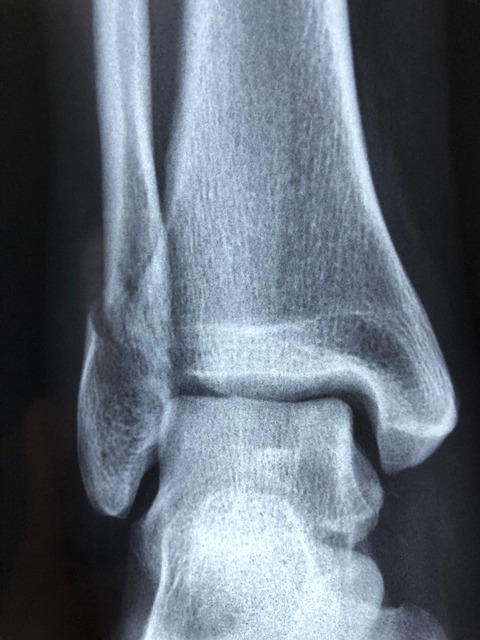

Co je to zlomenina kotníku a jak se léčí

Zlomenina kotníku je poměrně časté poranění, které může být velmi bolestivé a omezující. Kotník je kloub mezi kostmi dolní končetiny a zlomenina v této oblasti může ovlivnit vaši schopnost chodit normálně a provádět běžné denní aktivity. Léčba zlomeniny kotníku se zaměřuje na správné zarovnání kostí a jejich zahojení.